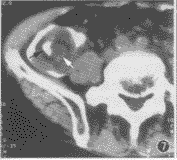

图7 慢性阑尾炎继发回结肠型肠套叠。可见靶征(白箭示肠壁炎变、增厚的阑尾,黑箭示套入的回肠)